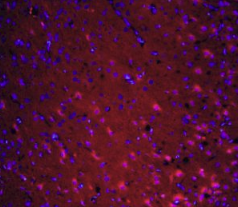

组织/细胞:大鼠脑组织;4%多聚甲醛固定石蜡包埋;

抗原回收:柠檬酸缓冲液(0.01M,pH 6),15min煮沸浴;37℃下封闭缓冲液(正常山羊血清)20分钟;

孵育:抗坏血性多克隆抗体,未结合1:200,4°C下过夜;二级抗体为山羊抗兔IgG,37°C下1:200稀释40分钟的Cy3结合。用DAPI(5ug/ml,蓝色)染色细胞核。